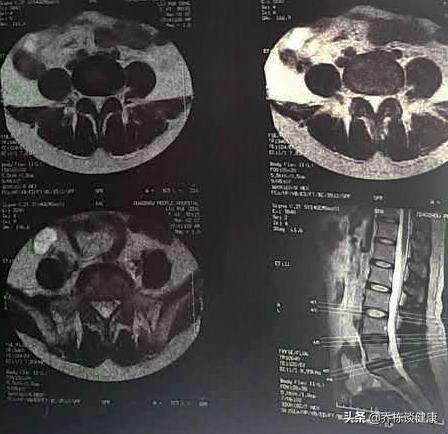

Les patients souffrant d'une hernie discale lombaire ne peuvent pas être vus sur le film, car le disque n'est pas visible sur le film, le film ne peut voir que l'os vertébral et l'espace vertébral, mais le disque n'a pas de hernie et la taille de la hernie ne peut pas être trouvée par le film.

Si un patient souffre d'une hernie discale et souhaite voir l'étendue de la hernie discale et la compression de la moelle épinière et des racines nerveuses dans le canal rachidien, il est nécessaire de procéder à un examen par tomodensitométrie ou par résonance magnétique de la zone correspondante, car seuls la tomodensitométrie et la résonance magnétique permettent de déterminer l'étendue de la hernie discale et de voir plus clairement la compression de la moelle épinière et des racines nerveuses dans le canal rachidien.